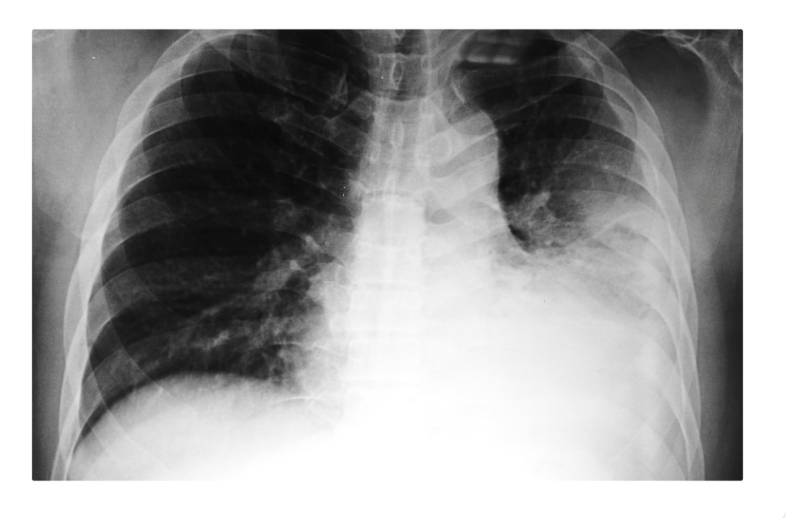

This CXR and scenario of a women who did not finish abx due to recent PNA. What dx?

empyema